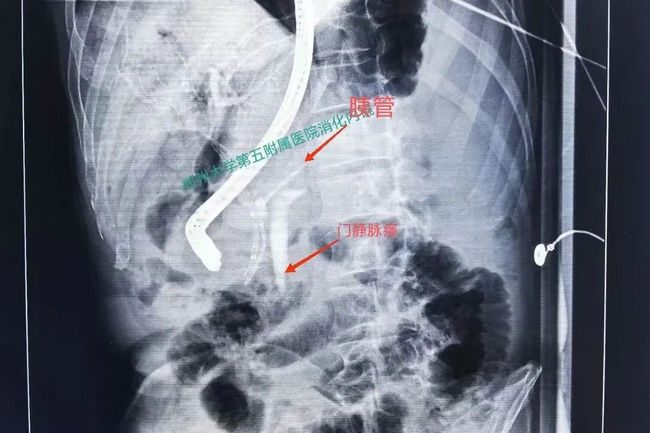

由于术中插管难度非常高,单是进导丝就花费了整整半个多小时,在导丝进入胆管后,郑权主任当机立断,保留导丝,使用第二根导丝反复试探胰管方向,终于顺利进入胰管并造影,此时门静脉立即显影,该患者的诊断明确了,的确存在胰腺-门静脉瘘。明确诊断后,郑权主任成功为其放置胰管支架来引流渗漏的胰液,顺利结束手术。术后陈先生恢复顺利,腹痛、腹水症状得到缓解,刘谦副主任医师、于政洋医师的精心诊治下,陈先生目前逐渐康复。